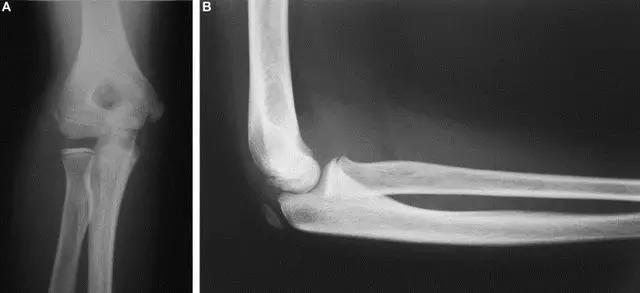

6. Hahn-steinthal 骨折

全肱骨小头骨折,为一种少见的关节内骨折,多见于成年人。常由于跌倒时手过度伸直或在屈肘时因桡骨小头撞击肱骨小头,并同时有外翻力存在时发病,亦可伴有滑车骨折与内侧副韧带的撕裂。X 线表现为全肱骨头骨折,向上移位。

Hahn-steinthal 骨折 X 片(来源:Hahn-Steinthal fracture: a case report.BioMed central Cases Journal20081:239)

Hahn-steinthal 骨折 CT 片(来源:Hahn-Steinthal fracture: a case report.BioMed central Cases Journal20081:239)